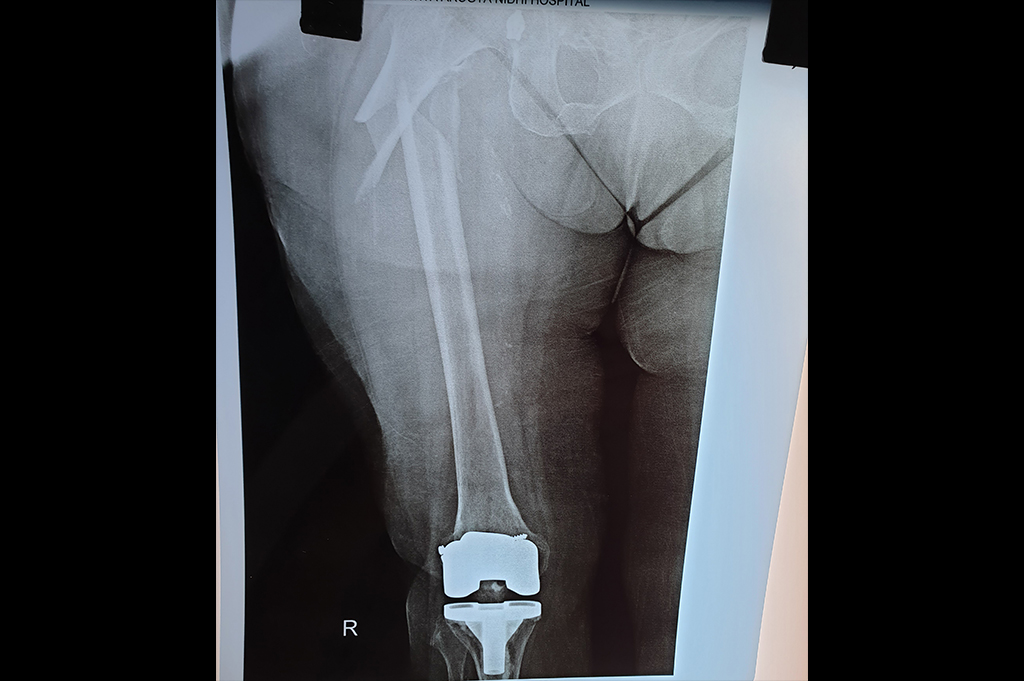

Total Knee Replacement - TKR